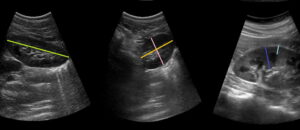

УЗИ почек: зачем делают, как проходит исследование и что показывает